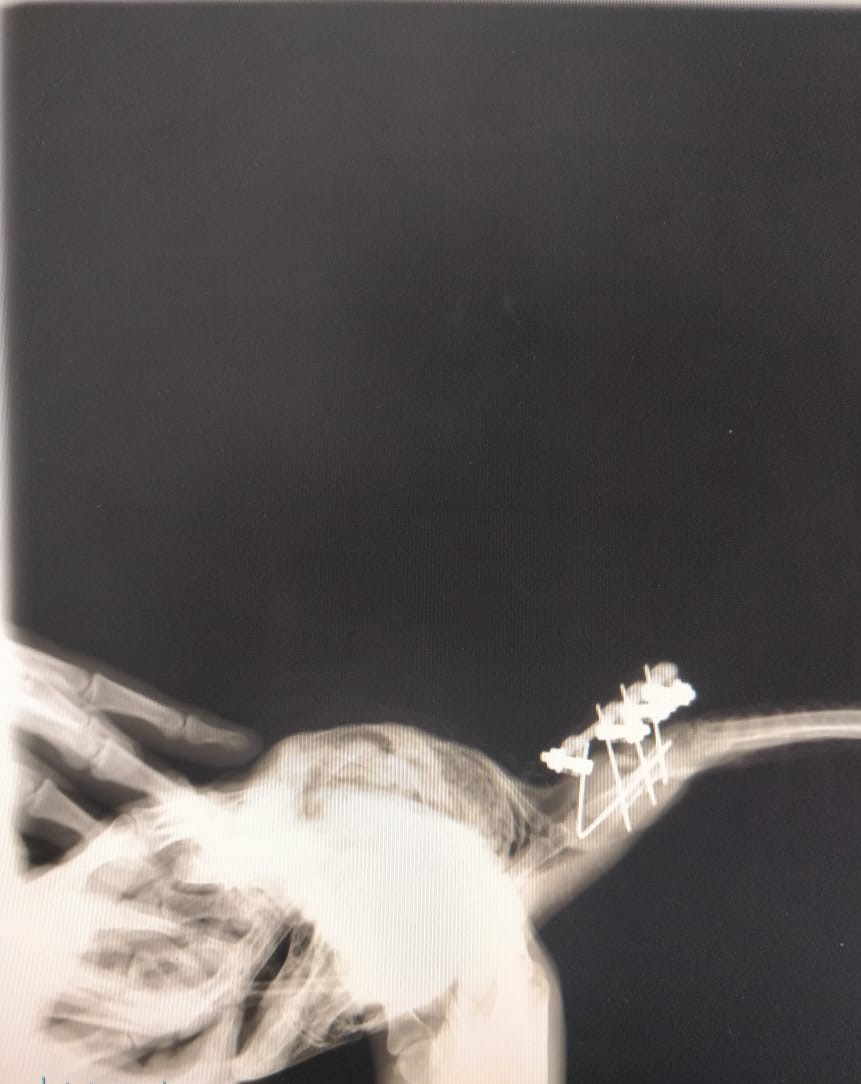

“Assim que constatamos a fratura em asa, o animal passou por um processo de estabilização com bandagem e ficou no aguardo do procedimento cirúrgico. Entramos em contato com a Clínica Dupet, que prontamente aceitou a parceria, e, assim, conseguimos marcar uma cirurgia de Osteossíntese de Úmero, com a parceria do Dr. Plínio Montalvani. Graças à eficiência de toda a equipe que participou, o procedimento cirúrgico na arara-azul-de-lear foi um sucesso”, explica Márcio, que também é médico veterinário do Inema.